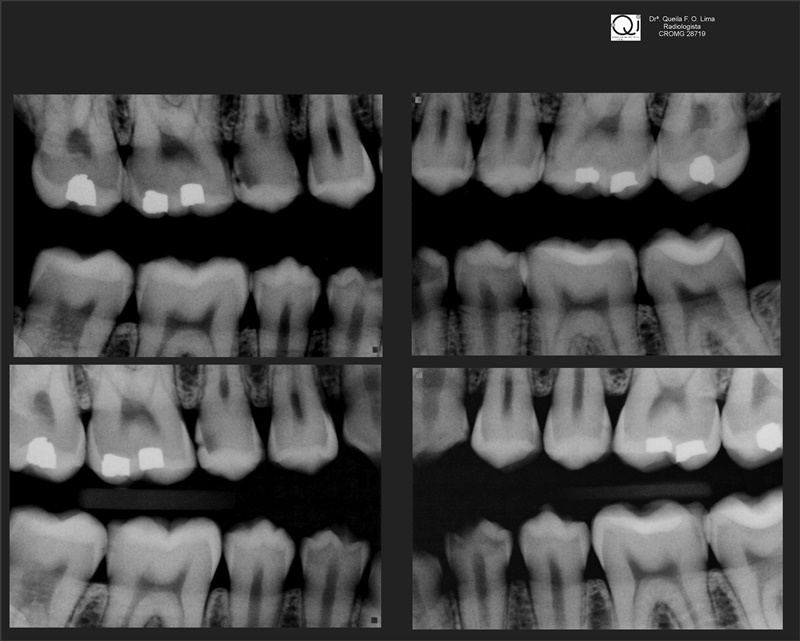

Radiografia Interproximal

Este exame radiográfico visualiza as faces proximais dos dentes posteriores observando-se simultaneamente as coroas dentárias dos dentes superiores e inferiores, e é indicado para a pesquisa de:

- cáries (proximais e incipientes).

- excesso ou falta de materiais restauradores.

- reabsorção da crista óssea alveolar (indicativa de doença periodontal).

Radiografias Interproximais (Com Aparelho Extra Bucal)

Realizada como uma única tomada panorâmica. Indicada para crianças abaixo de 07anos e demais pacientes, com dificuldade para a realização dos exames periapicais e interproximais, intrabucais (técnica convencional).